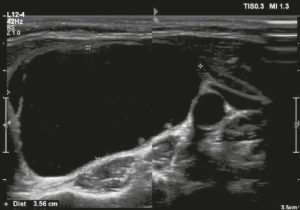

Ở đây, chúng tôi cung cấp các ví dụ minh họa việc áp dụng thực tế hệ thống ACR TI-RADS (Hình 18, 19, 20, 21). Các chú thích dưới hình mô tả chi tiết các mục đã được đánh giá và hiển thị điểm số trong ngoặc đơn.

Hình 19. Hình ảnh nhân giáp dạng đặc (2 điểm), giảm âm rất mạnh (3 điểm), rộng hơn cao (0 điểm), có bờ trơn láng (0 điểm), và không có các ổ tăng âm hay bóng lưng (0 điểm). Do đó, tổng điểm là 5 điểm và mức độ nguy cơ được phân loại là TR4.